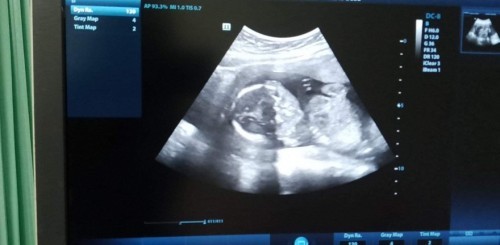

อยากเห็นหน้าน้องของคุณแม่แต่ล่ะท่านจัง ของเรา19วีคนะคะ คุณหมอบอกน้องไม่ให้เห็นเพศค่ะ

บ้านนี้ก็ไม่ให้เห็นหน้าค่ะ ให้เห็นแต่แขนกับขา เพศก็แทบจะไม่ได้เห็น